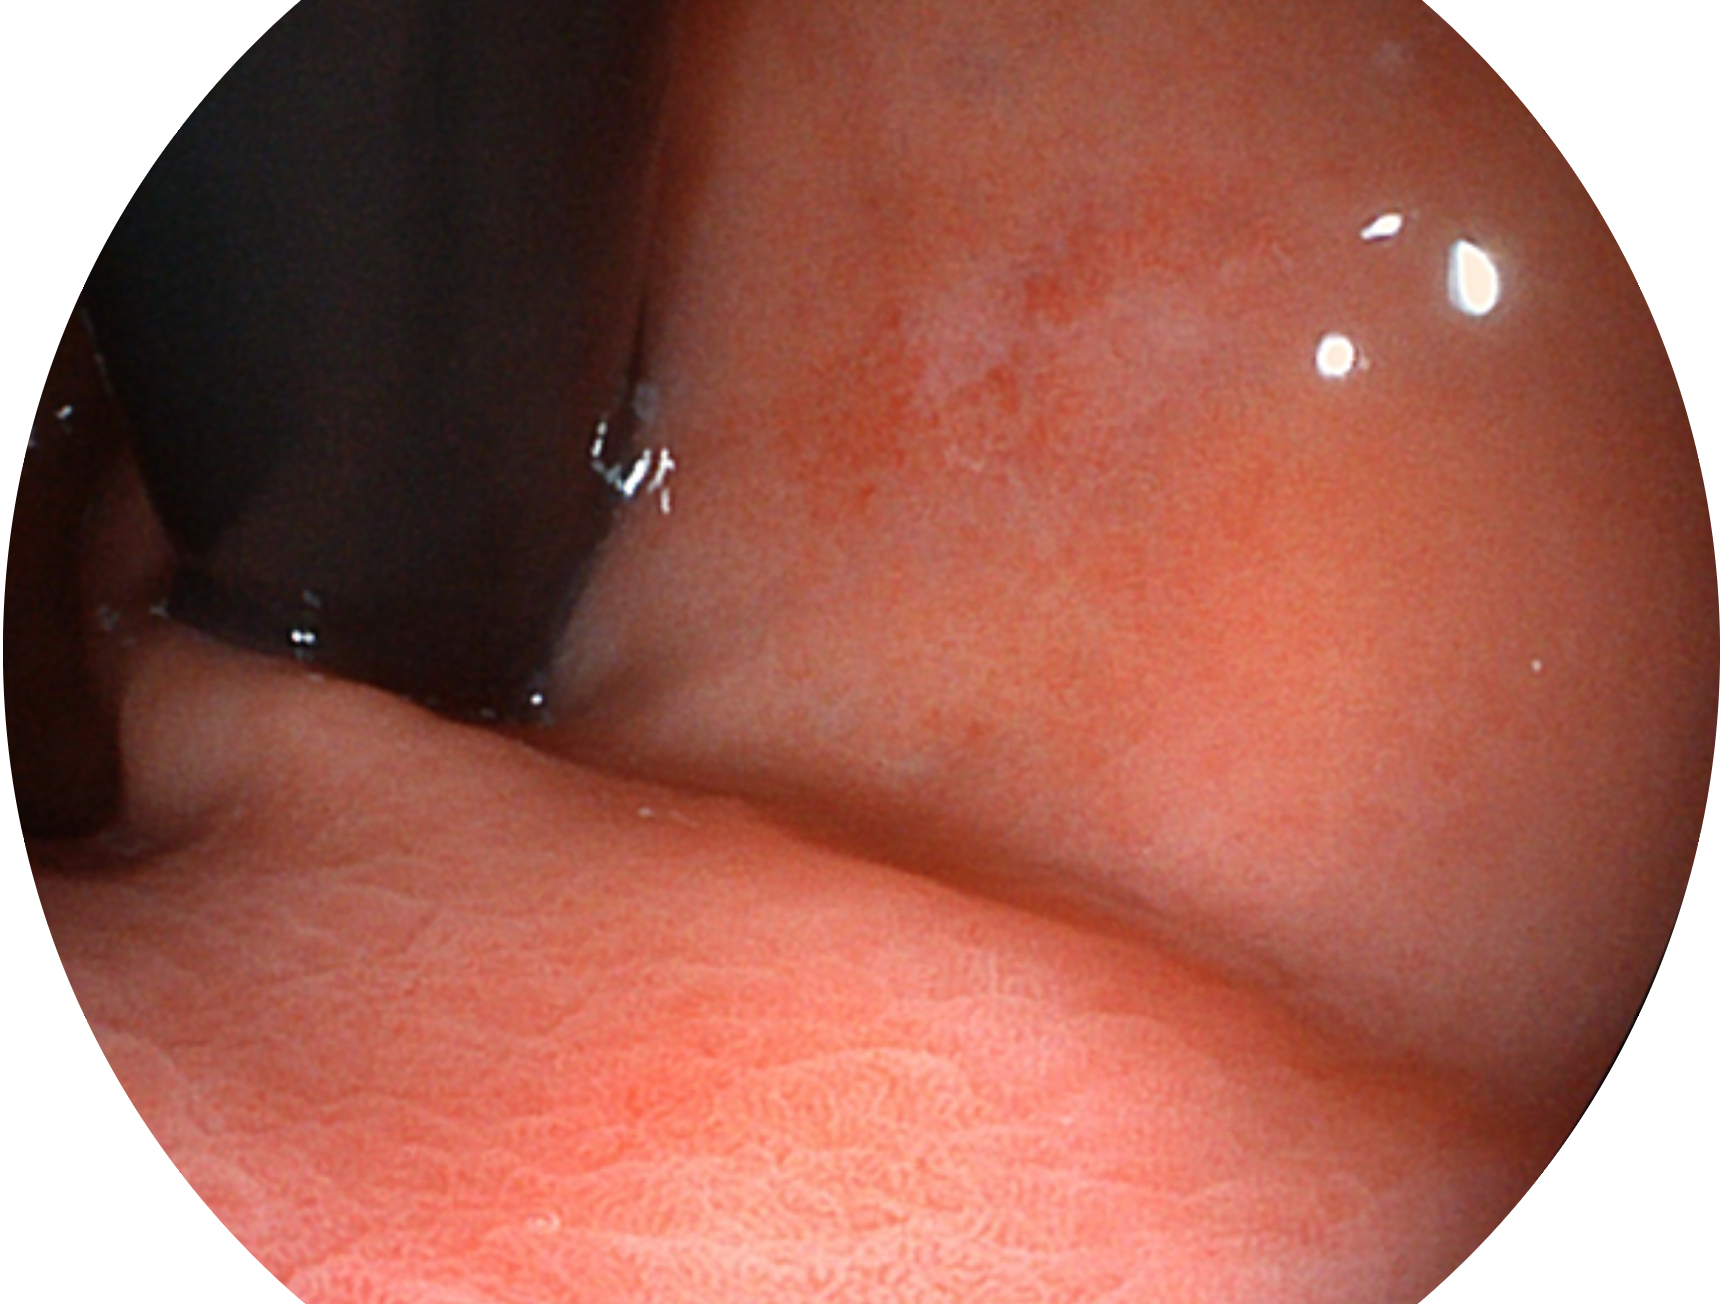

新葡的京集团8814检测站新开发的内镜染色技术,主要是基于多波长LED 光源的开发,VLS-55Q 四波长LED 光源是由四个不同颜色的LED光按照相应照明模式所规定的特定发光比例进行合束后形成,合束后形成的照明光的光谱由红光、绿光、蓝光及蓝紫光这四个不同的波段范围构成。具有更高光谱自由度,通过光谱比例的控制,实现了聚谱成像技术,英文全称为“Spectral Focused Imaging, SFI”,缩写为“SFI”和光电复合染色成像技术,英文全称为“Versatile Intelligent Staining Technology, VIST”,缩写为“VIST”。